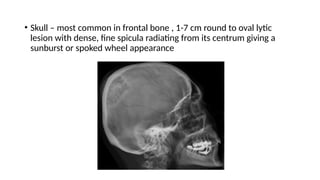

• Skull – most common in frontal bone , 1-7 cm round to oval lytic

lesion with dense, fine spicula radiating from its centrum giving a

sunburst or spoked wheel appearance